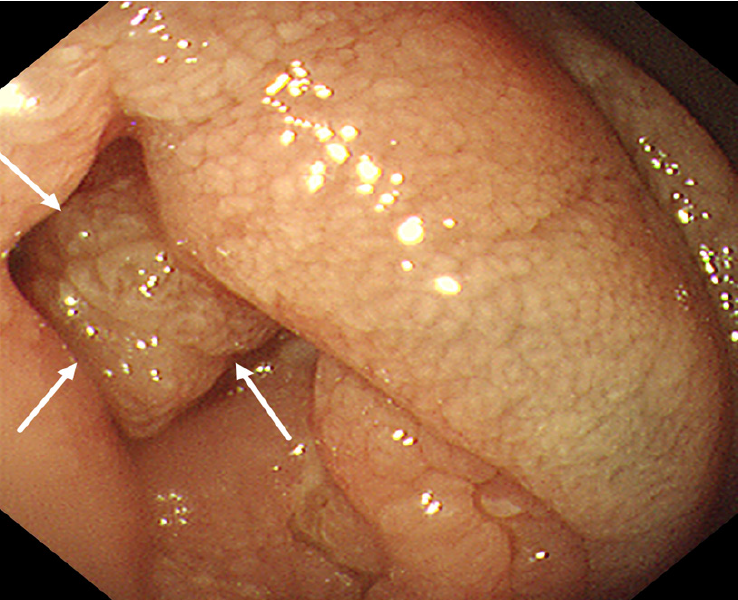

18F-FDG PET/CT revealed multiple segmental thickening in the descending and horizontal segments of the duodenum, jejunum, and ileum. The horizontal segment of the duodenum had the largest lesion, approximately 5 cm × 4 cm in size. The intestinal tract showed aneurysmal dilatation with stenosis and obstruction of the intestinal lumen, and the maximal standardized uptake value (SUVmax) was 9.2 (Figure 1). The SUVmax reflects the uptake of 18F-FDG and the metabolic activity of the lesion. Multiple enlarged lymph nodes were found in the abdominal and pelvic mesentery. The largest lesion was 0.9 cm × 0.7 cm in size, with an SUVmax of 3.1 (Figure 1). A plain MR scan of the upper abdomen revealed that the larger lesion in the horizontal segment of the duodenum presented an iso-signal on T1 weighted imaging (T1WI) and an iso- or hypo-signal on T2WI. It was hyperintense on diffusion-weighted imaging, and the apparent diffusion coefficient was 0.8 × 10-3 mm2/second. Post-contrast MR imaging (MRI) demonstrated delayed and homogeneous enhancement (Figure 2). Gastroduodenoscopy revealed cauliflower-like masses in the duodenal lumen, marked narrowing and obstruction of the intestinal lumen (Figure 3).

MEITL should be differentiated from Crohn’s disease (CD), intestinal B-cell lymphoma and intestinal carcinoma in imaging diagnosis. The present patient presented with multiple segmental thickening of the small intestine, similar to the imaging findings of “skip distribution” in patients with CD. Although CD also manifests as intestinal wall thickening and FDG uptake, there is no obvious intestinal dilatation. Epelboym et al[14] reported that the average SUV ratio (SUVmax/liver SUVmean) in eight patients with CD before treatment was 3.16 (range 1.88-4.6). The SUV ratio in our patient was 5.4, which was greater than that in patients with CD. On contrast-enhanced CT, CD may present enlargement and thickening of the mesenteric vessels. Moreover, the onset of CD is gradual, and the course of the disease is relatively long, CD can be complicated by abscesses and fistula formation and can involve extraintestinal organs, such as the mouth, eyes and joints[15]. The characteristic finding of CD under endoscopy is cobblestone-like ulceration[15]. Most intestinal B-cell lymphomas are localized lesions, and the SUVmax (mean ± SD) of B-cell lymphoma (14.1 ± 6.4) is significantly greater than that of T-cell lymphoma (7.6 ± 3.9)[16], which is helpful for their differentiation. The focus of intestinal carcinoma is relatively limited, causing focal intestinal concentric stenosis or asymmetric intestinal stenosis. Intestinal carcinoma rarely involves multiple segments; however, it is prone to invade the surrounding fat space and adjacent organs and hematogenously metastasize to the liver and lungs. MEITL is more likely to manifest as aneurysmal dilatation at multiple sites and generally does not result in fat space infiltration around the intestine.